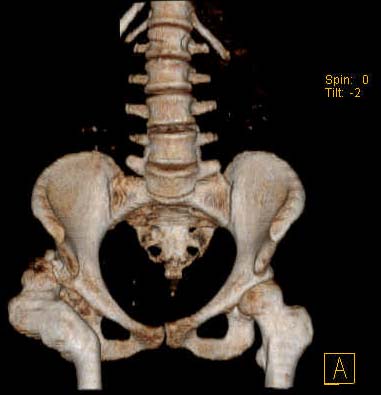

Уважаемые коллеги!Женщина, 35 летВ прошлом по поводу врожденного вывиха бедра перенесла операцию остеотомии по Шанцу

с удлинением правой ноги за счет бедра на уровне диафиза. В последнее время прогрессируют боли в правом тазобедренном суставе, порочное положение правой ноги, затруднена ходьба.Вопросы:1) Целесообразно ли эндопротезирование правого тазобедренного сустава?2) Целесообразный ли следующие действия: канал бедренной кости предполагаем вскрыть для введения ножки протеза на высоте угловой деформации, предполагаем низведение большого вертела с мышцами; протез будет подобран индивидуально, предполагается умеренная версия?В приложении рентгенограммы и трехмерная КТ.В цветном и более качественном варианте КТ размещена здесь